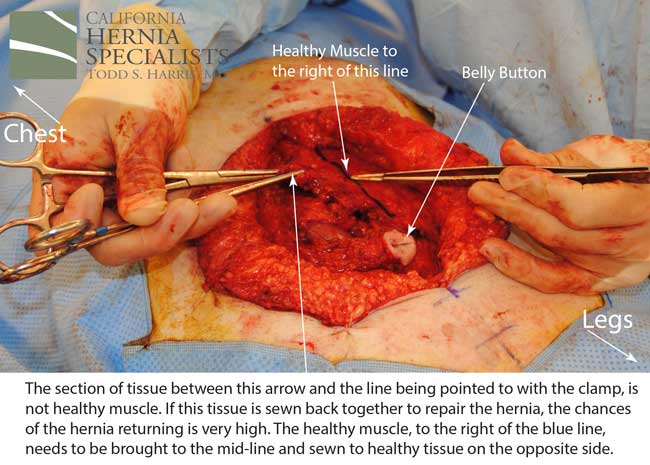

After this CT scan was obtained, a lengthy discussion with the patient was undertaken to explain the reasons for the prior hernia repair failures, and to explain all the options. By simply returning to the operating room and putting in more mesh, and sewing it to unhealthy muscle, we would not be actually repairing the hernia.

The more complete approach would be to bring healthy muscle together at the mid line. Only after the muscle is repaired completely, can a mesh be used to SUPPORT the muscle repair. Meshes should not be considered a bridge from healthy muscle to healthy muscle. Instead mesh should be used as a reinforcement of a correct hernia repair.

This technique requires more surgical time, recovery time, and usually several days in the hospital. However, this patient chose to proceed with the open hernia repair. Below are some of the pictures from his surgery as well as post operative CT scan image and photos of the patient.